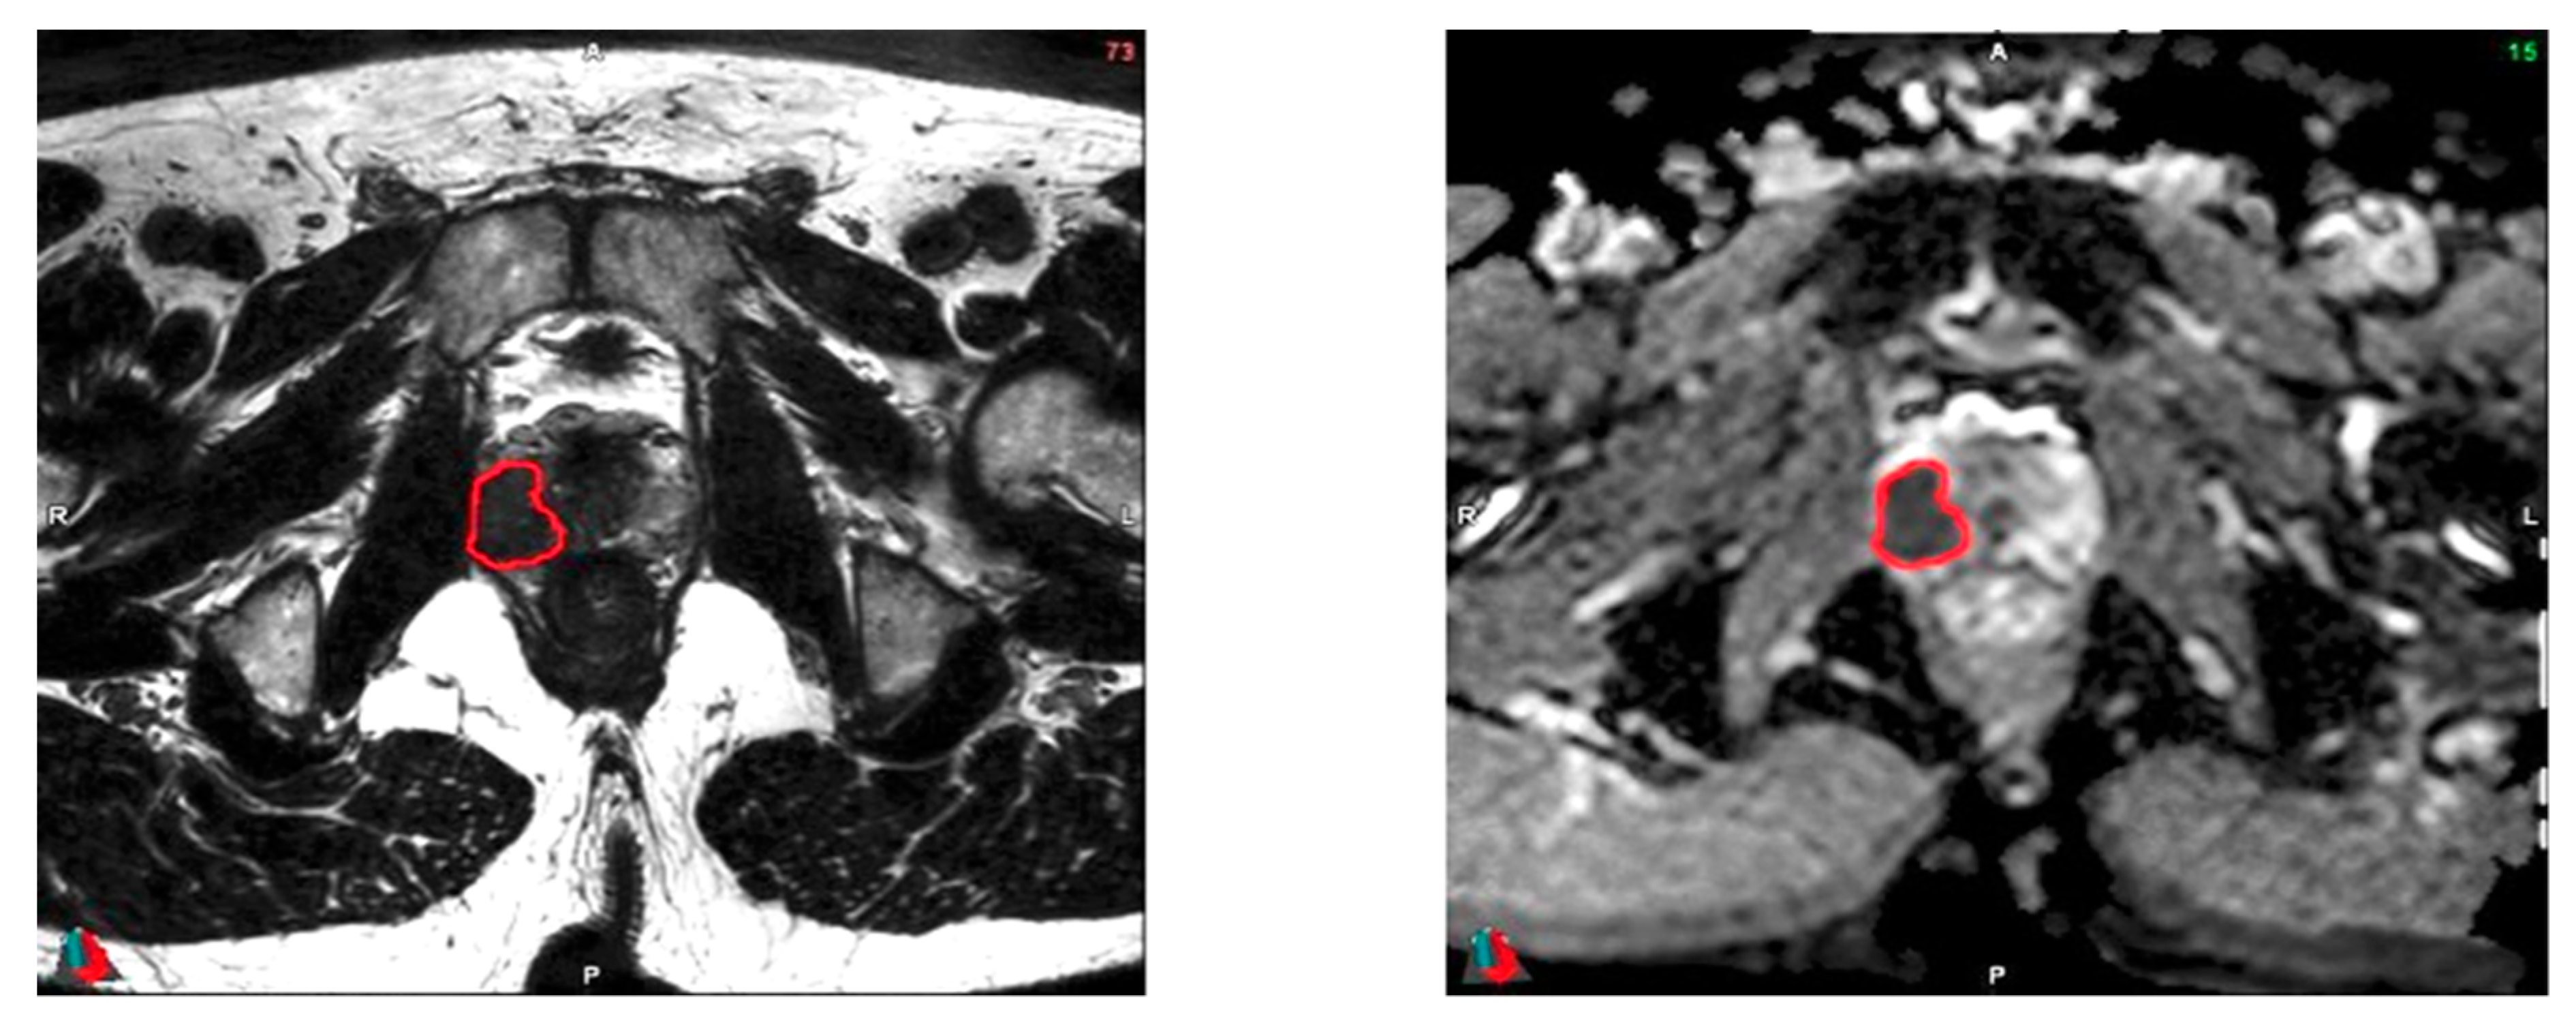

2.6. Tumor Delineation

2.7. Radiomics Features